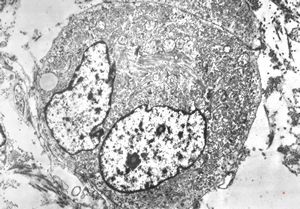

F,32y. | transversally sectioned skeletal muscle cell

mouse skeletal muscle cell - transversal section